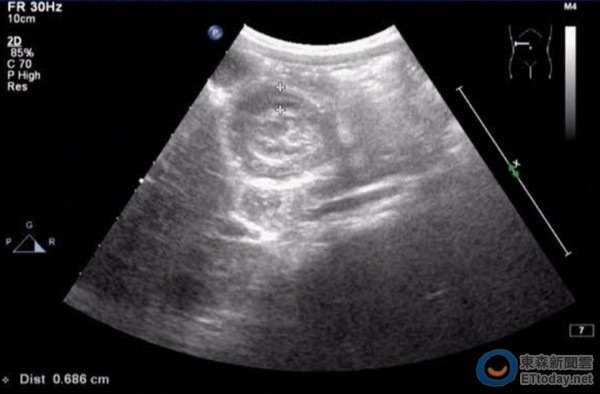

▲類過敏紫斑引起腸套疊之靶子圖形。(圖/國泰醫院提供)

林隆煌說,和紫斑同時出現的腹部症狀,包括嘔吐、腹絞痛、血便,嚴重時甚至會出現腸胃道大量出血、腸套疊或穿孔,曾經有病童因紫斑「太晚」出現,被誤診為闌尾炎進而切除盲腸。罹患關節型紫斑的病童,則會出現反復性的腳踝、膝蓋、手肘、手腕等腫痛反應,所幸痊癒後不會影響關節變形。